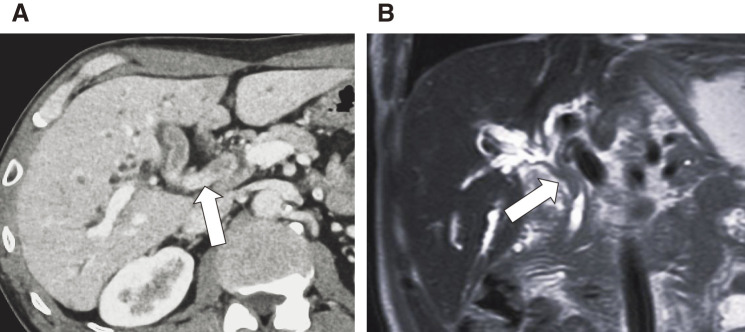

Case presentation: A 70-year-old man was diagnosed with hilar CC (cT3N1M0, Stage III C) based on biopsy of the common bile duct stenosis and computed tomography (CT) and magnetic resonance cholangiopancreatography scans. Initially, a right lobe hepatectomy and subtotal stomach-preserving pancreatoduodenectomy were planned. However, there were concerns about an insufficient functional remnant liver volume. Trans-ileocolic portal embolization of the right portal vein branch was performed. On a preoperative CT scan 1 month later for liver volumetry, swelling of the para-aortic lymph nodes was observed, which was judged as distant metastasis, and radical resection could not be performed. After 8 courses of durvalumab plus gemcitabine and cisplatin therapy, vanishing fluorodeoxyglucose accumulation in the para-aortic lymph nodes was observed on positron emission tomography-CT. The possibility of resection was reevaluated, and a right lobe hepatectomy and extrahepatic biliary reconstruction were performed as conversion surgeries. Histological examination confirmed the absence of residual tumors or lymph node metastases. Ten months after surgery, the patient was free of recurrence.